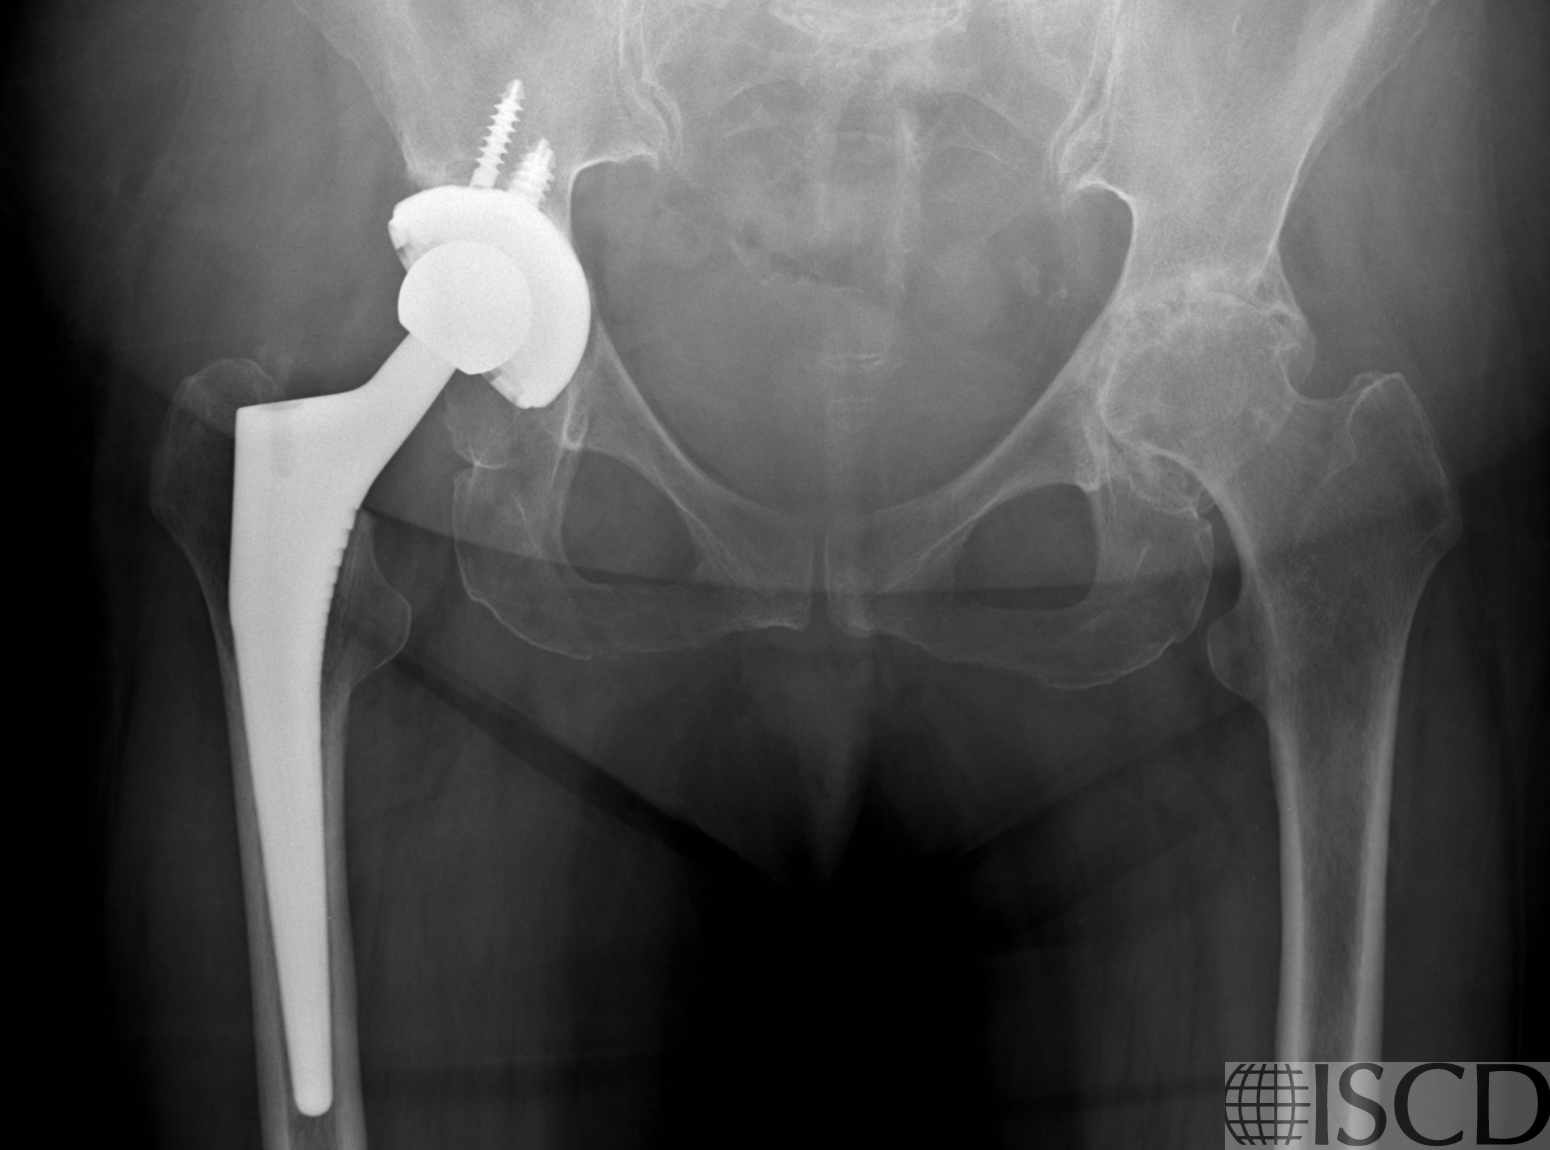

There is a black hole artifact over L4, therefore it was omitted from analysis. There are black hole-type artifacts over L4 and in the soft tissue.

This radiograph shows the tantalum clips overlying L4 that are responsible for the black hole artifact on the Hologic lumbar spine scan.

This Hologic lumbar spine DXA scan shows a black hole-type artifact over L4. Items like lead bullets and tantalum clips show up as “black”on Hologic scans. The accompanying radiograph shows the clips over L4. L4 is omitted because of overlying artifacts.

Black hole artifacts occur with dense metals such as lead and tantalum on a Hologic scan. Other metals, like stainless steel, don’t produce black hole artifacts. Presumably there is complete attenuation of both Kev peaks so the difference is zero, making the image appear black. Lead bullets are measured as having high bone mineral content (BMC) and appear black in the dual-energy mode on the Hologic scanner and blue as artifact on GE Healthcare scanners. Black hole artifacts over bone are handled differently between Hologic and General Electric. With the Hologic scanner, when a dense artifact overlies bone, the BMC associated with that artifact is excluded, but the bone area is not altered. Consequently, the bone mineral density (BMD) of the affected vertebra, and of L1-4 is decreased. The GE scanners exclude both the associated BMC and area covered by the artifact, thereby minimizing the impact on BMD. Dense artifacts in the soft tissue do not significantly affect BMD on either manufacturer’s densitometer on phantom experiments., however, further experiments need to be done to verify this finding.